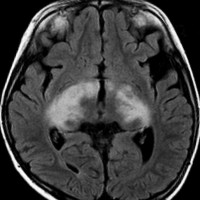

視索に限局する毛様細胞性星細胞腫

左の視索の内部から発生したもので,これも単神経・視神経膠腫と同様によくみるものです。左の画像で視神経交叉が全く侵されていないのがわかります。

単視神経膠腫は全摘出できるのですが,このタイプは外側膝状体へ及ぶので完全摘出ができません。部分摘出と定位放射線治療が適応となります。